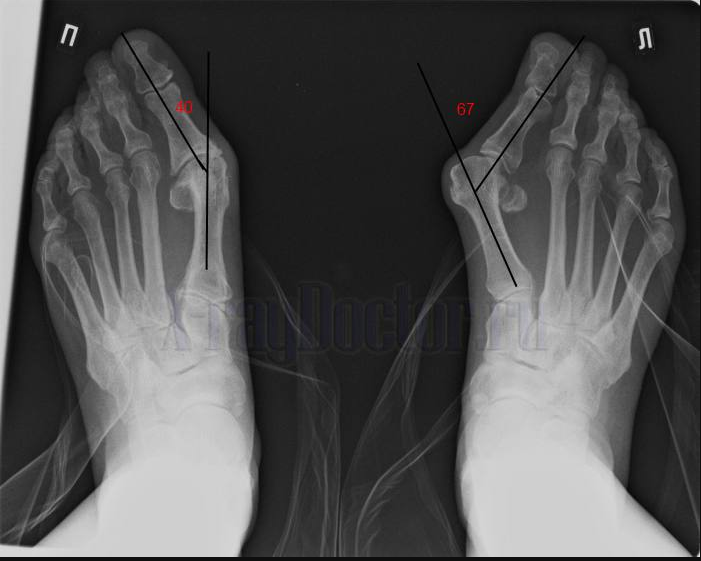

Степень поперечного плоскостопия определяется углом между осью первой плюсневой кости и первой фалангой большого пальца (HV-угол):

I степень (слабовыраженная): Угол <20°. Визуально стопа выглядит нормально, но пациенты отмечают усталость после длительной ходьбы и дискомфорт в узкой обуви. На рентгене — начальные признаки подвывиха в плюснефаланговом суставе.

II степень (умеренная): Угол 20–35°. Появляется видимая «косточка» у основания большого пальца, боли усиливаются при ношении каблуков. На подошве формируются стойкие натоптыши под II‑III плюсневыми костями.

III степень (тяжелая): Угол >35°. Большой палец «наезжает» на соседние, сустав деформирован, движения резко ограничены. Из‑за перегрузки центральных отделов стопы развивается метатарзалгия — острая боль при малейшей опоре на ногу.